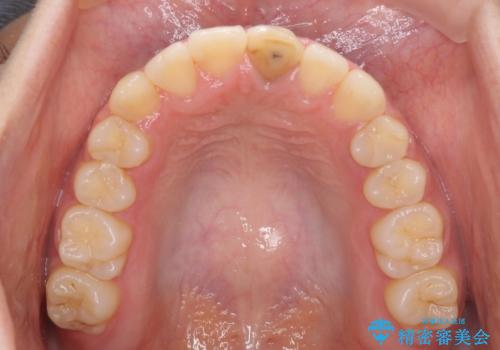

前歯の反対咬合 非抜歯のワイヤー矯正

1年半はかかると思っていた治療期間ですが、反対咬合となっている前歯が思いの外早く動き、僅か9ヶ月で終了させることができました。

前歯を気にせず笑えるようになり、患者様には大変満足していただきました。